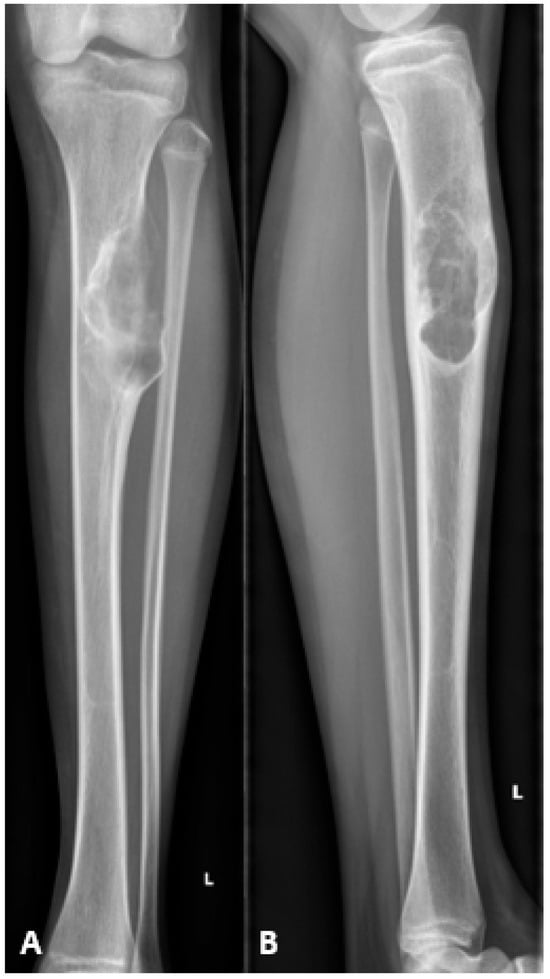

Figure 1.

Preoperative radiographs showing an osteofibrous dysplasia-like adamantinoma (OFD/LA) in the left tibial diaphysis. (A) Anteroposterior view. (B) Lateral view.